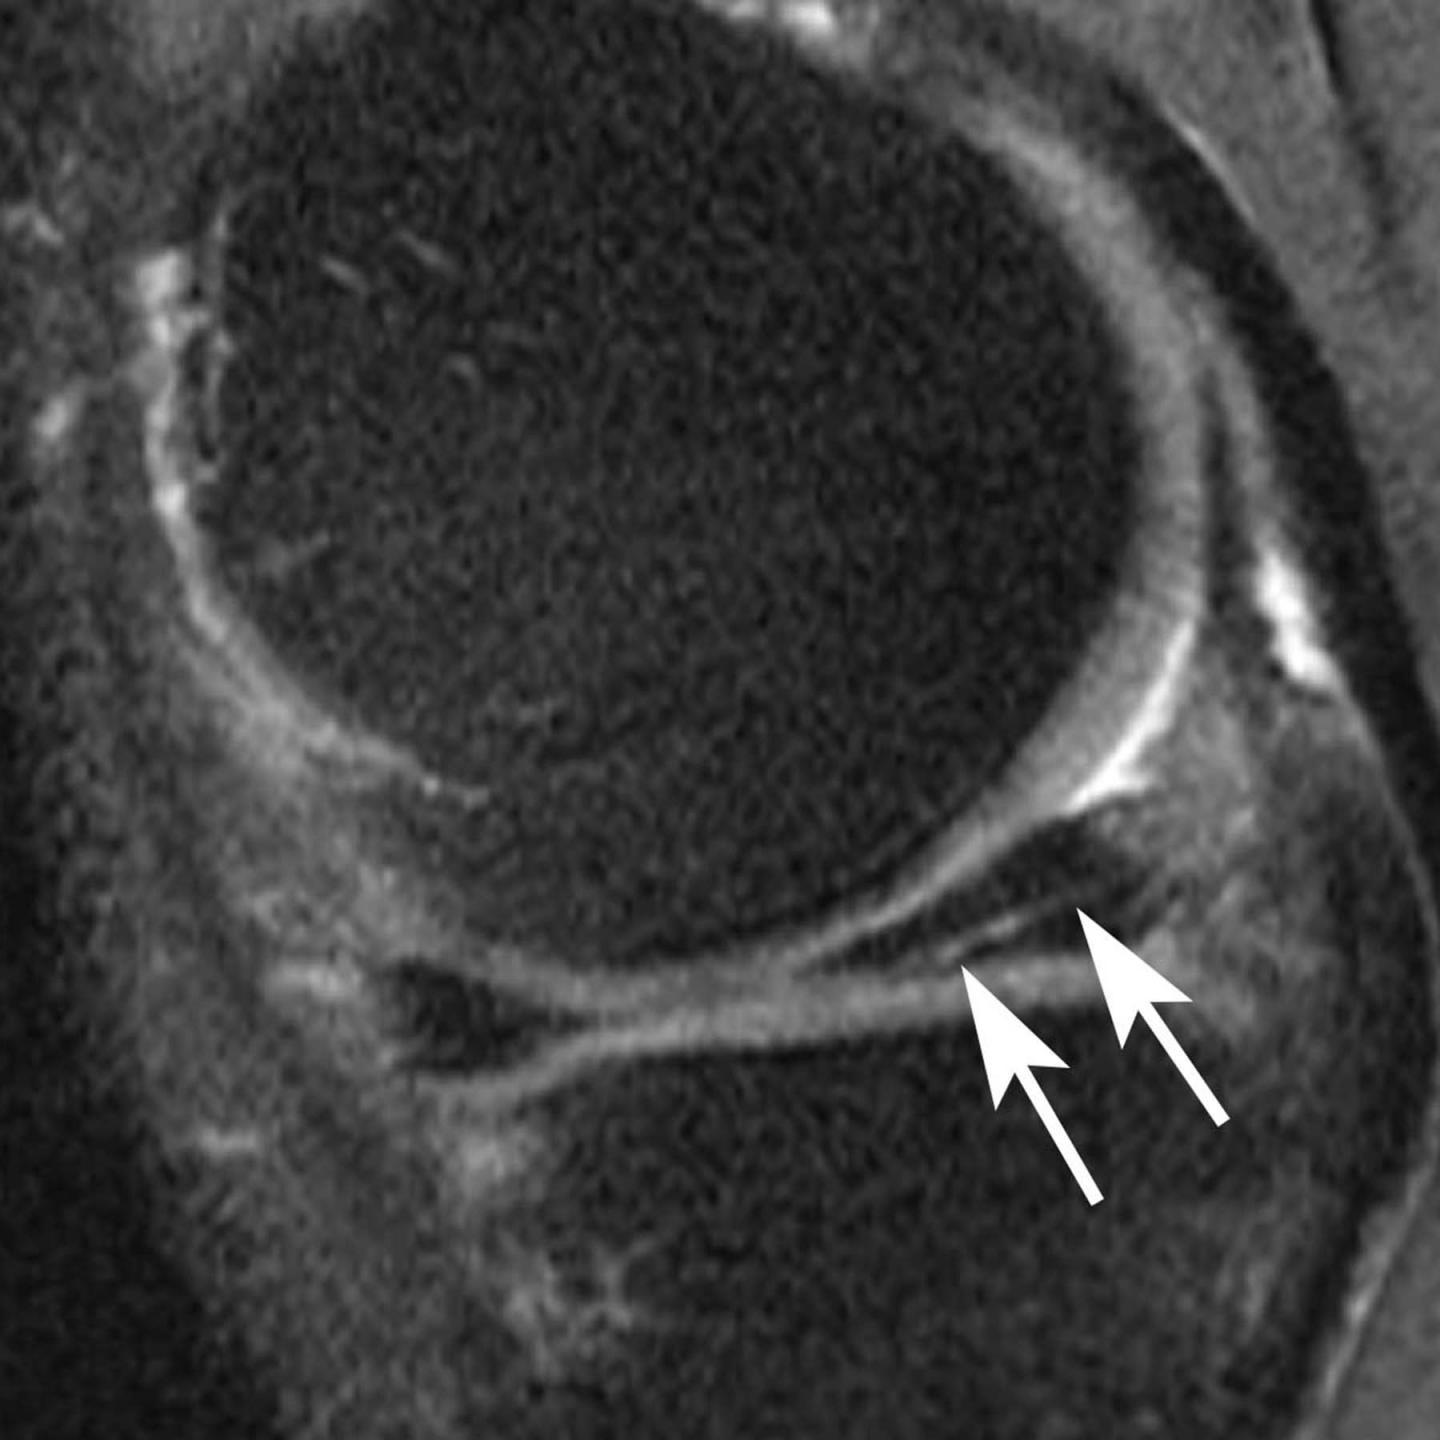

This sagittal intermediate-weighted fat-saturated image post surgery shows substance loss of the posterior horn of the medial meniscus (large arrows) and concomitant cartilage loss at the central medial tibia and femur (small arrows).

(Photo Credit: RSNA)